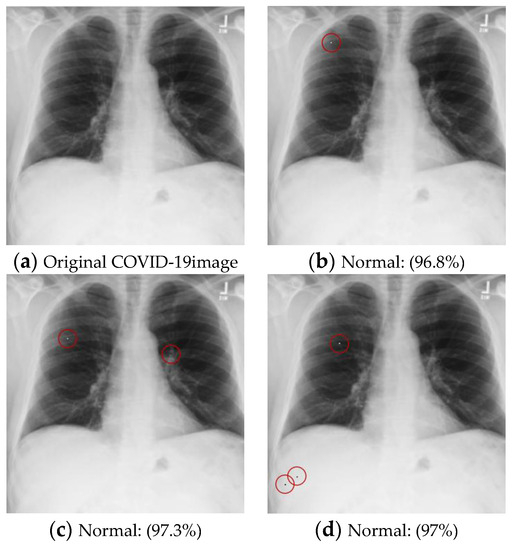

• Diseased images to Normal images

This dataset contained two diseases: “Pneumonia” and “Covid”. The goal was to perturb a pixel in the original disease image and turn it into a normal image. Since the attacked image had to be classified as “Normal”, this was a targeted attack. The test dataset belonging to “Pneumonia” and “Covid” was attacked, and the results were evaluated based on the Success Rate and Average Confidence Level. A further experiment was conducted on two- and three-pixel attacks to understand the influence of the number of perturbed pixels on the performance of the victim model, and the results are shown in Table 12. The examples of attack images are shown in Figure 7.

Figure 7. Examples of the attack results on the COVID-19 dataset with confidence level of ResNet50: (a) The original COVID-19 image; (b) One-pixel attack; (c) Two-pixel attack; (d) Three-pixel attack.